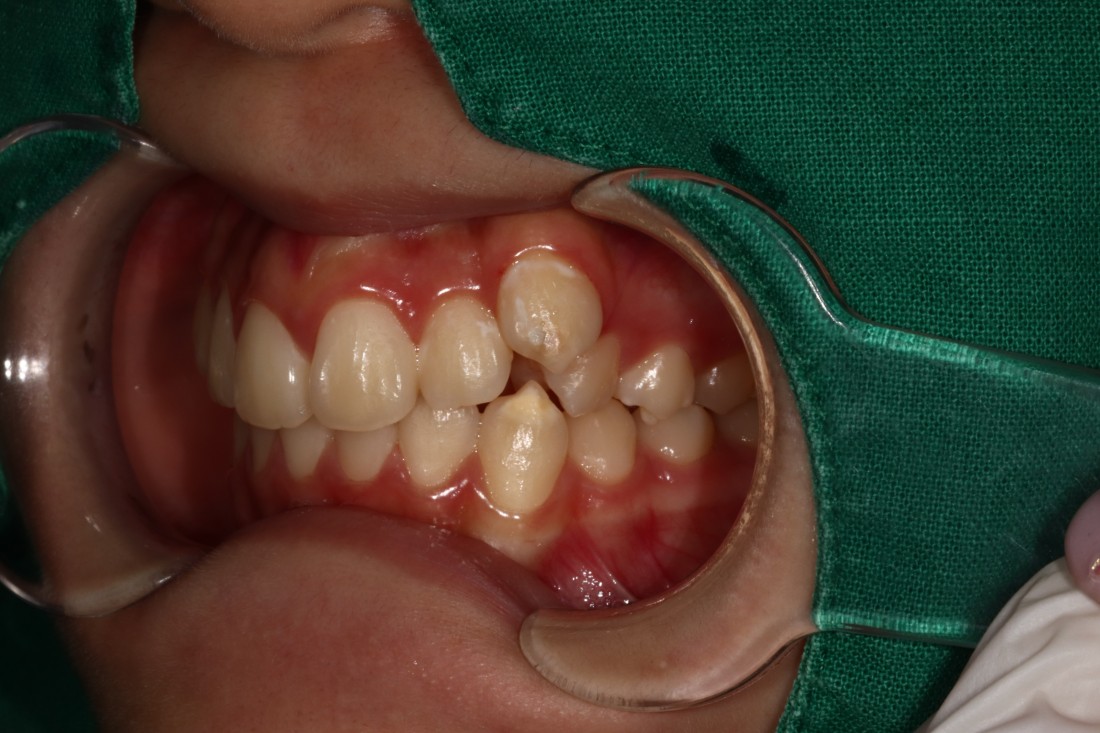

때로는 치아교정만으로 해결하는 것 보다

임플란트 식립을 동시에 해서

더욱 최상의 치료결과를 얻을 수 있을 때가

생기는데요.

20년 경력의 교정전문의 진료와 함께

구강외과 전문의 대표원장님의

협진도 동시에 진행하여

치아교정 기간을 단축하고

성공적으로 고른 치열을 완성하였습니다.